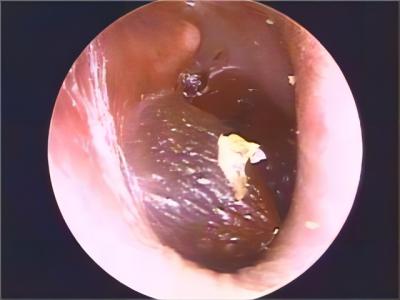

鼓膜炎的首发症状为外耳道剧痛,并可有轻度听力下降。随后,由于大疱破裂而有稀薄血性分泌物从外耳道流出;由于病变限于鼓膜的上皮层,未波及纤维层,故大疱破裂后无鼓膜穿孔。

由于鼓膜炎疼痛较重,可对症给予镇痛药物。针对病毒感染,可口服阿昔洛韦等抗病毒药物。在大疱破裂前局部用具有消炎镇痛的苯酚甘油滴耳液。局部激光理疗可促进炎症吸收。当大疱破裂后,不能再用苯酚甘油滴耳,可用抗生素滴耳液预防继发感染。